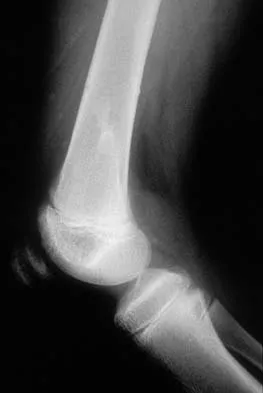

Figures 7a and 7b show the radiographs of a 51-year-old woman who injured her left leg after falling off a stepladder. Surgical reconstruction is performed with a compression screw and side plate; the postoperative radiograph is shown in Figure 7c. Following gradual progression of weight bearing, she reports that she slipped again and placed full weight on the extremity. She now notes a new onset of increased pain in her left thigh and hip region. Follow-up radiographs are shown in Figures 7d and 7e. Reconstruction should consist of

The initial fracture was an unstable reverse oblique intertrochanteric fracture with subtrochanteric extension. Initial fixation with a high-angled screw and side plate construct may not provide stability as well as a 95 degree fixed-angle device or a intramedullary hip screw device. The follow-up radiographs show loss of fixation and further propagation of the fracture distally. Reconstruction would best be accomplished with hardware removal and conversion to a long intramedullary nail with femoral head fixation or a 95 degree angled plate and screw device. Conversion to a longer plate does not improve the biomechanical situation at the primary fracture site. In situ bone grafting would not provide any additional stability and would not correct the deformity. The proximal femoral fracture is not amenable to retrograde nailing. Cerclage wiring will not sufficiently enhance stability and is not indicated. Bridle SH, Patel AD, Bircher M, Calvert PT: Fixation of intertrochanteric fractures of the femur: A randomized prospective comparison of a gamma nail and dynamic hip screw. J Bone Joint Surg Br 1991;73:330-334. DeLee JC: Fractures and dislocations of the hip, in Rockwood CA Jr, Green DP, Bucholz RW, Heckman JD (eds): Rockwood and Green's Fractures in Adults, ed 4. Philadelphia, PA, Lippincott-Raven, 1996, pp 1659-1825. Haidukewych GJ, Israel TA, Berry DJ: Reverse obliquity fractures of the intertrochanteric region of the femur. J Bone Joint Surg Am 2001;83:643-650.